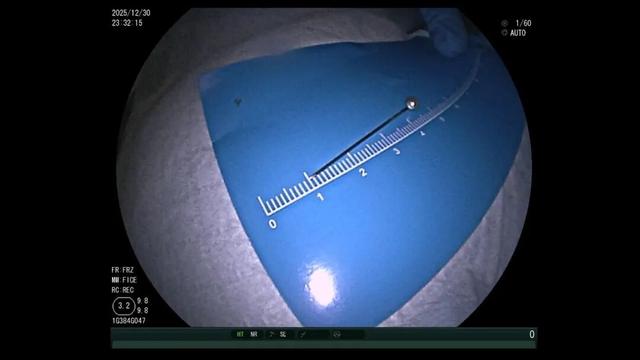

面对这些棘手情况,消化内科迅速联合儿科和普外科制定方案,经过30分钟的专注搜寻,医生终于锁定了大头针的针尖位置——它正静静“躺”在食物残渣中,银色的针尖格外显眼。

一开始,医生尝试用异物钳、网兜抓取,但大头针太滑,几次尝试都失败了。紧急调整方案后,医生改用圈套器,在透明帽的辅助下,小心翼翼地将大头针调整为竖直方,避免取出时横向划伤食管。

医生一边指导孩子配合,一边稳稳操控圈套器,将大头针牢牢固定。随着内镜缓缓退出,大头针终于被完整取出,全程未造成任何黏膜损伤。